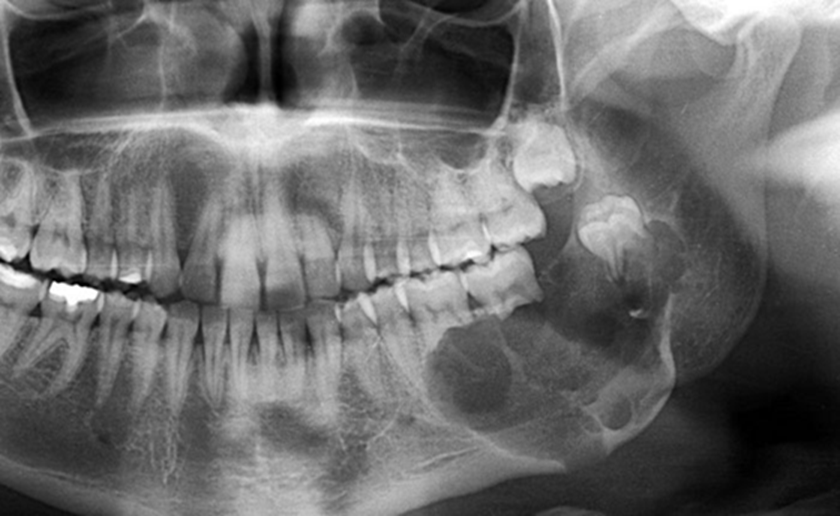

Hình X-quang chẩn đoán ung thư xương hàm

Biến chứng nguy hiểm nhất là nhiễm trùng lan rộng, gãy xương hàm bệnh lý do xương bị phá hủy, và đặc biệt là di căn xa nếu khối u mang tính chất ung thư. Ung thư xương hàm có thể lan tới phổi, gan hoặc hạch bạch huyết. Khi bệnh được phát hiện muộn, việc điều trị trở nên phức tạp, phải kết hợp phẫu thuật cắt bỏ rộng, xạ trị hoặc hóa trị. Tỷ lệ tử vong phụ thuộc vào loại mô bệnh học và giai đoạn phát hiện. Với u lành tính, tiên lượng thường tốt nếu được phẫu thuật triệt để. Ngược lại, với ung thư xương hàm giai đoạn muộn, nguy cơ tử vong tăng cao do di căn và suy kiệt toàn thân.